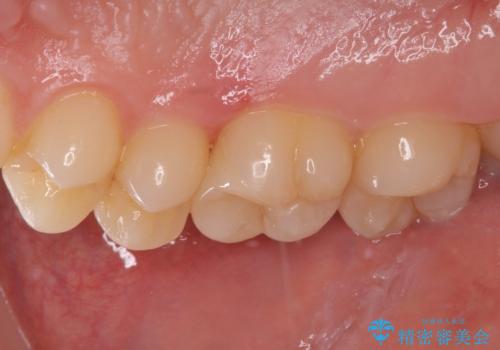

フロスが引っかかる セラミックインレーによるむし歯治療

- ウェブサイトの症例(https://seimitsushinbi.jp/case/9473/)を見て、同じようにフロスが引っかかるとのことで来院された患者様です。

虫歯を除去した後、セラミックインレーにて修復治療を行うこととしました。

セラミックインレー装着後はフロスの引っかかるストレスから解放され、患者様には大変満足していただきました。